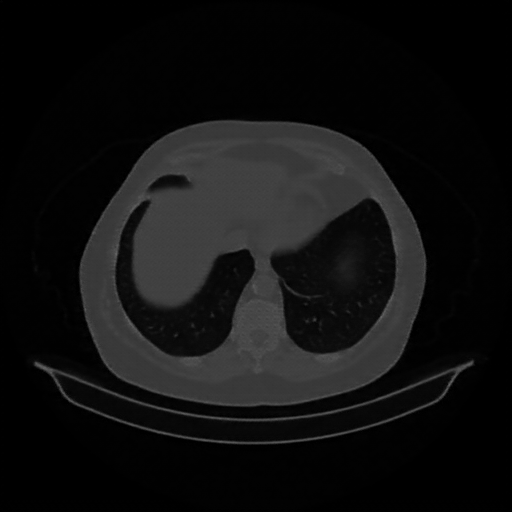

Generated VENOUS CT scan (A→B translation)

Full window (WL 1023.5, WW 4095 β†’ Low βˆ’1024, High +3071)

Lung window (WL -600, WW 1500 β†’ Low βˆ’1350, High +150)